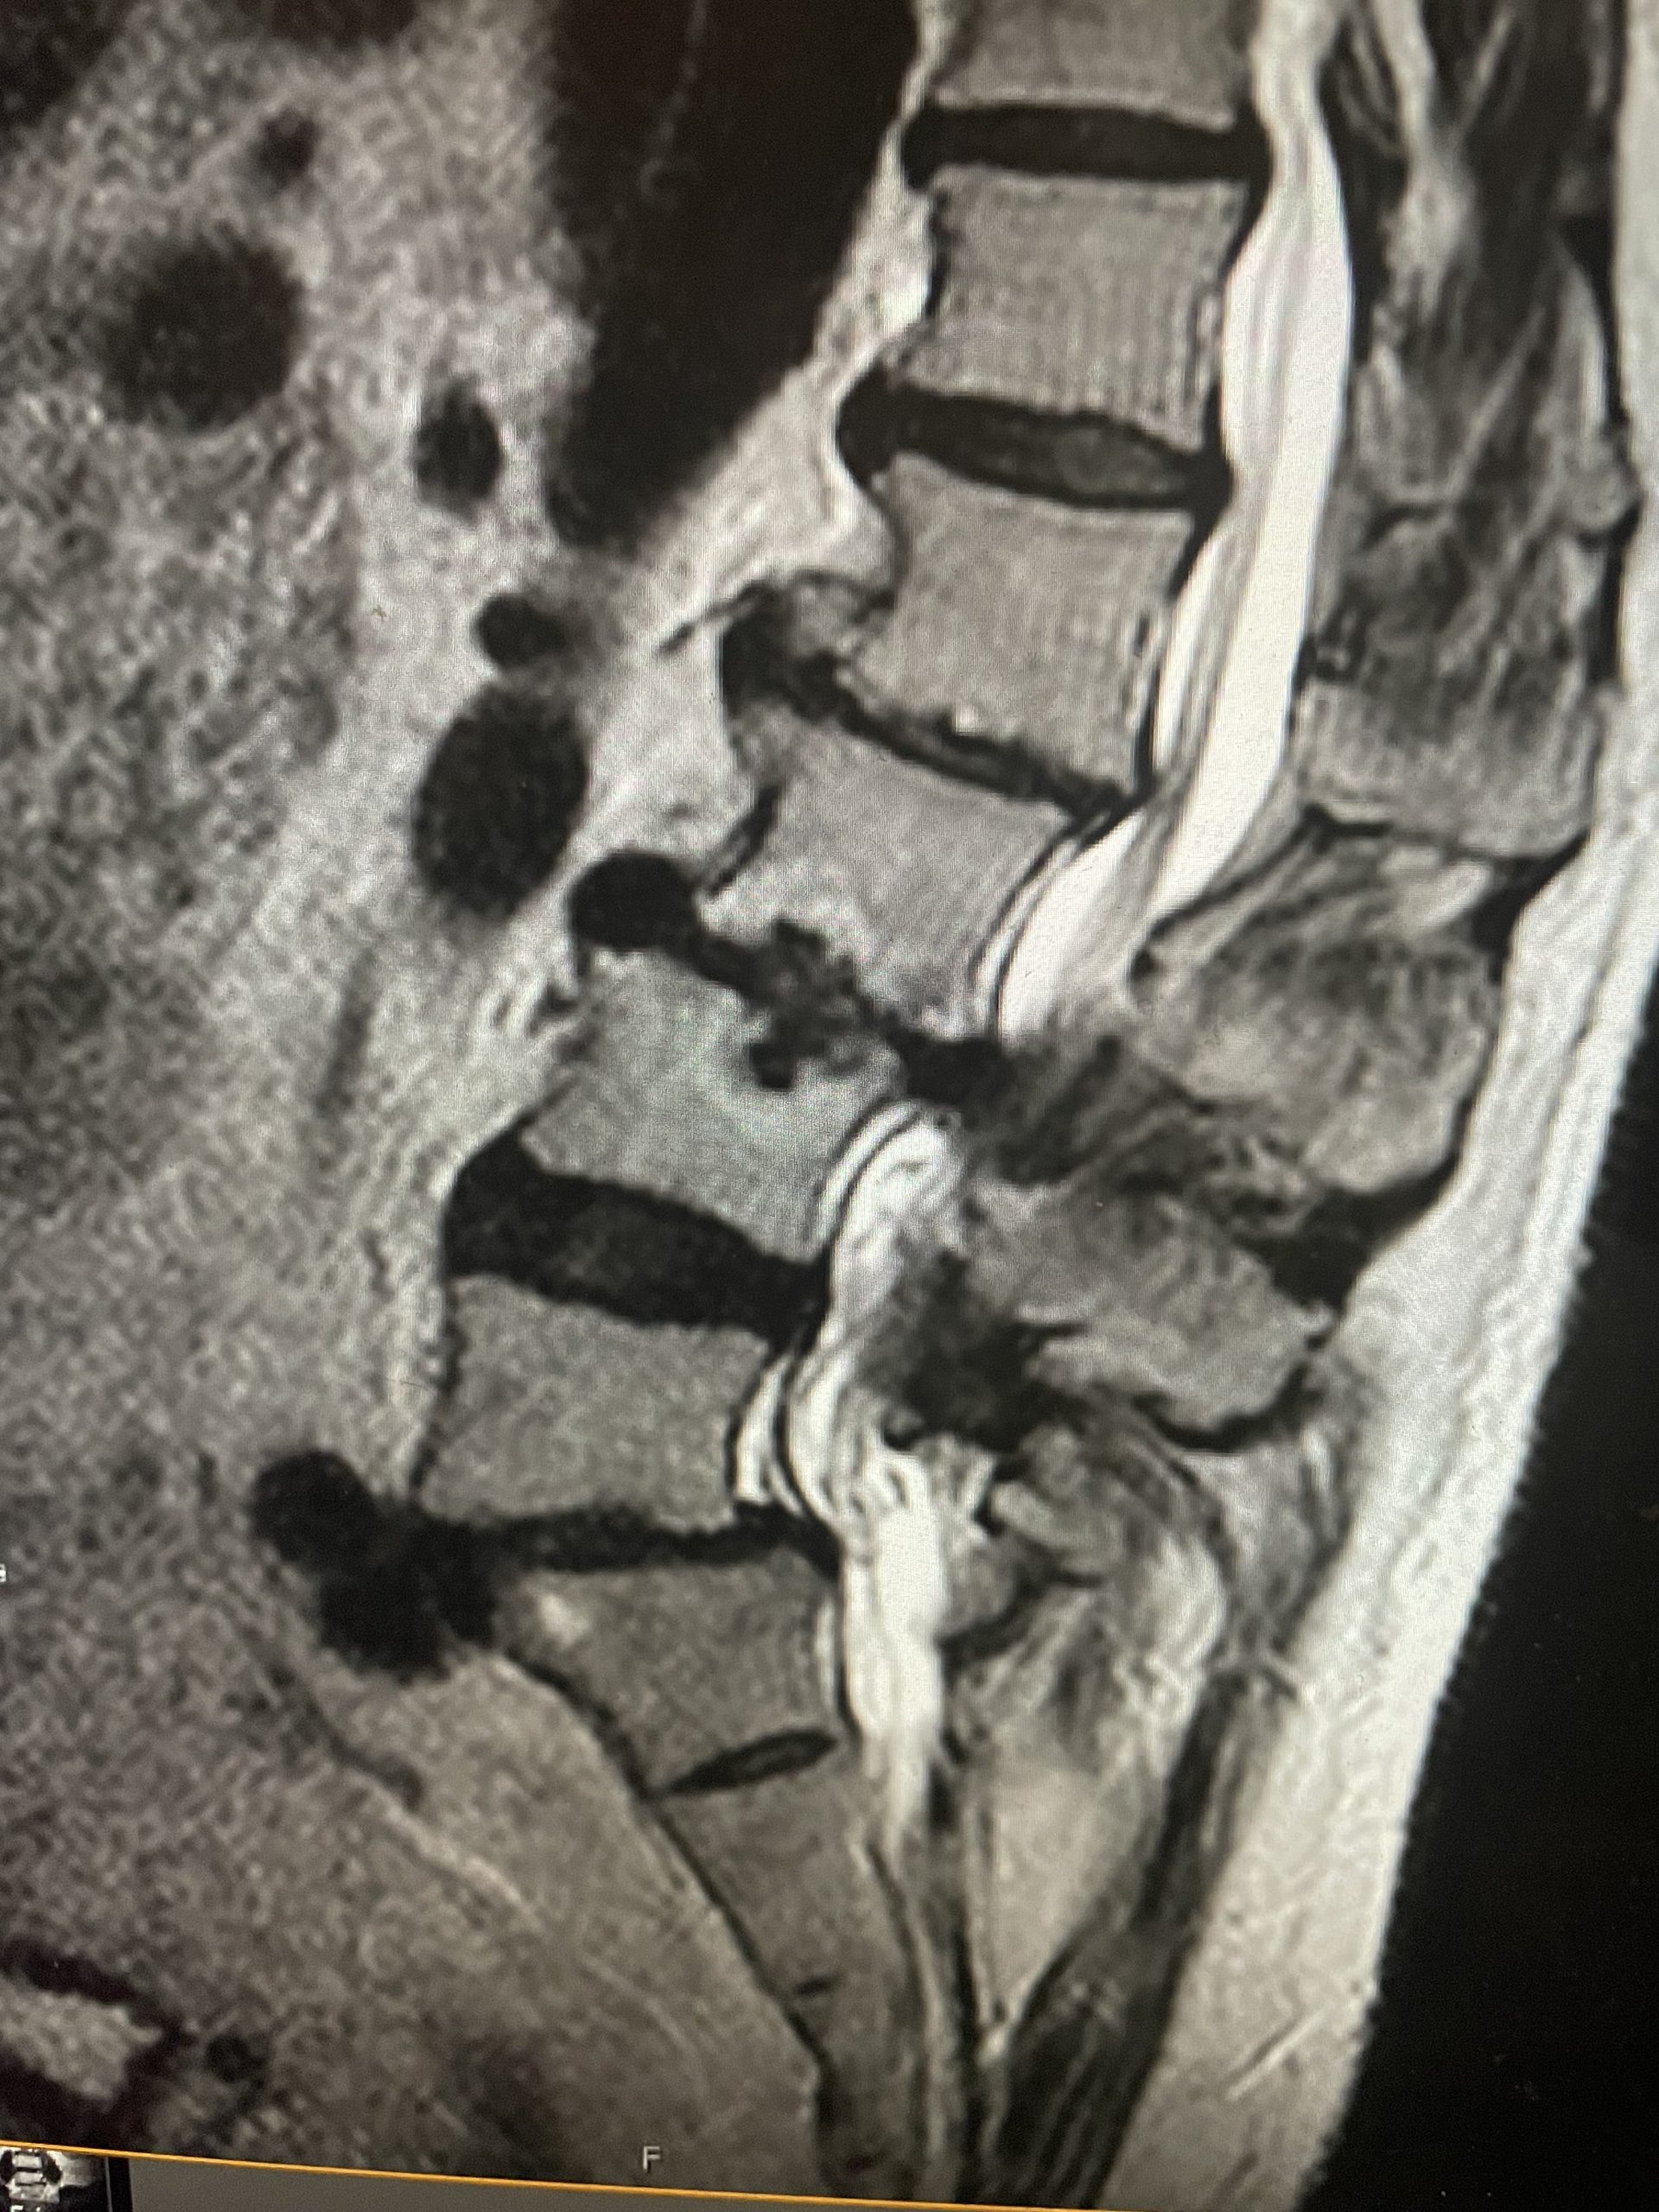

This 52 year-old female presents with 4 months of progressive neck pain, numbness of both hands, and difficulty using her hands and buttoning a shirt. She was noted to have mild right-sided weakness in a long track distribution which included her finger extensor, hip flexor, dorsiflexor weakness. She had tried chiropractic care. Imaging revealed a very large C4-5 disc herniation with severe cord compression which was more eccentric to the right, but also causing left-sided compression (Fig 1). The patient also had C5-6 disc collapse with biomechanical reduction of the C5-6 motion segment which puts more stress on the next segment. In essence the C5-6 is acting like it is autofused. This resulted in premature degeneration of the C4-5 segment which resulted in the disc herniation. It was decided, given a diagnosis of early cervical myelopathy with spinal cord compression, to offer an anterior cervical discectomy and fusion at C4-5 to decompress the spinal cord.